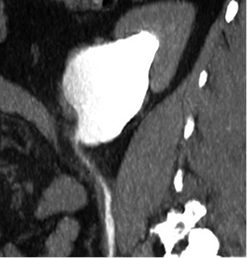

2019 m. gegužės 7 d. (praėjus apie 6 mėn. po operacijos) atlikta kompiuterinė tomografija (4 pav. B). Kairiojo inksto kolektorika kiek prasiplėtusi, geldelė iki ~42 mm pločio, kontrastinę medžiagą (k/m) skiria laiku, kontrastuojasi, k/m nuteka šlapimtakiu į šlapimo pūslę. Kairysis šlapimtakis neprasiplėtęs, proksimalinėje dalyje jo spindis iki 5,5 mm diametro, distalinėje dalyje – iki 7 mm. Ties šlapimtakio proksimaline dalimi matyti infiltruoti aplinkiniai audiniai (vertinama kaip pakitimai po buvusios operacijos). Kitų pakitimų šlapimo takuose nenustatyta.

2019 m. spalio 9 d. (praėjus apie 12 mėn. po operacijos), atlikus kompiuterinę tomografiją, matyti, kad kairiojo inksto geldelė mažiau išplėsta – iki ~26 mm pločio (buvo iki 42 mm), PUJ spindis – apie 2,5 mm pločio, distaliau šlapimtakis neišplėstas, jo spindis iki pat šlapimo pūslės išmatuojamas 3,5–5 mm, sienelės plonos, rentgenokontrastinių akmenų nematyti (4 pav. C). Ties PUJ periureteriniuose audiniuose – fibroziniai pakitimai, perinefriniuose audiniuose – dorzaliai riebalinio audinio ribotos pooperacinės sankaupos.

A

B

C

4 pav. Kompiuterinė tomografija (A – prieš operaciją; B – praėjus 6 mėn. po operacijos; C – praėjus 12 mėn. po operacijos)